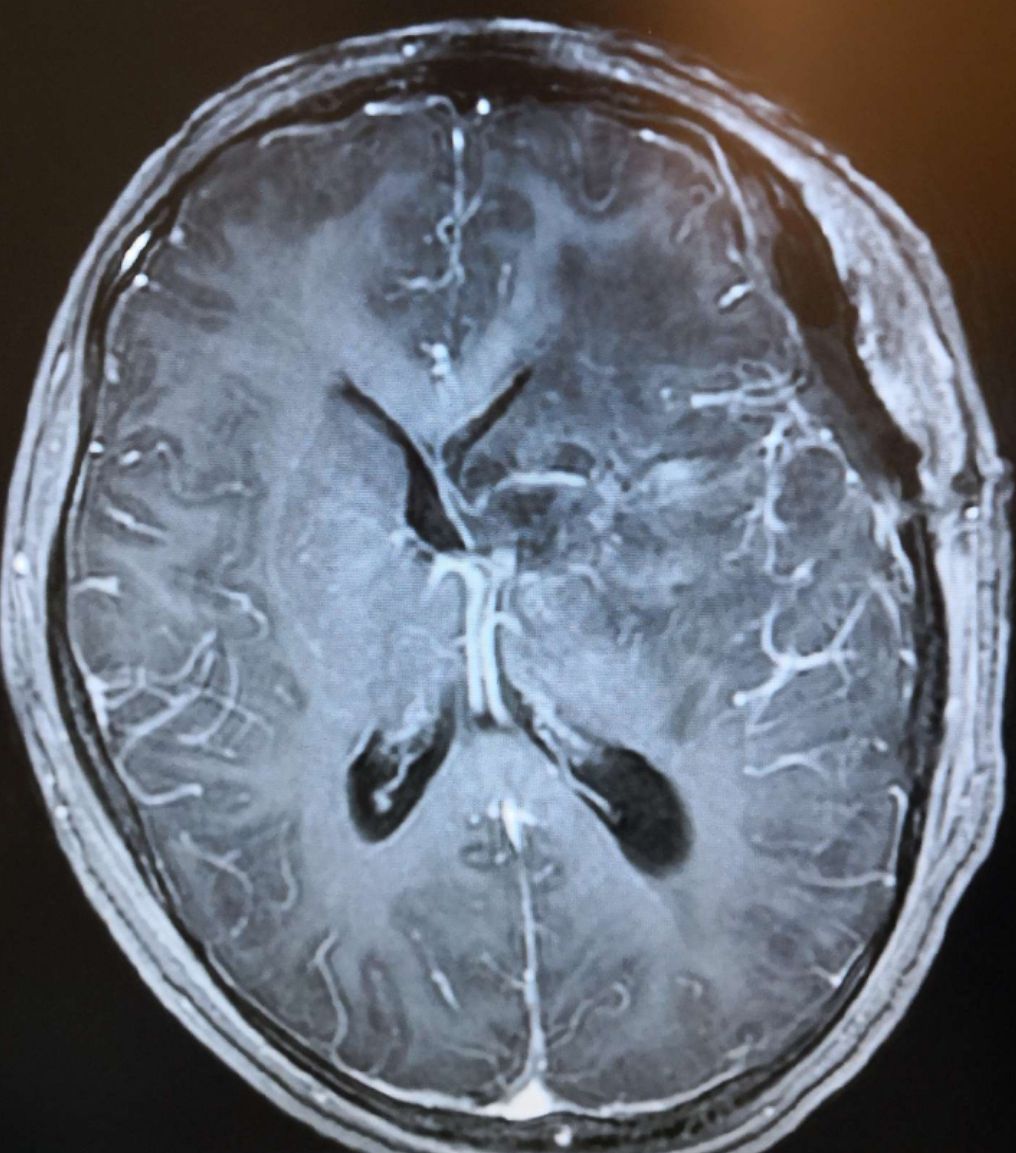

术后头颅MRI增强显示:左侧基底节未见强化病灶,中线居中,脑室轻度受压。

术后头颅MRI 增强扫描显示:基底节未见强化病灶,脑室轻度受压,中线恢复正常。